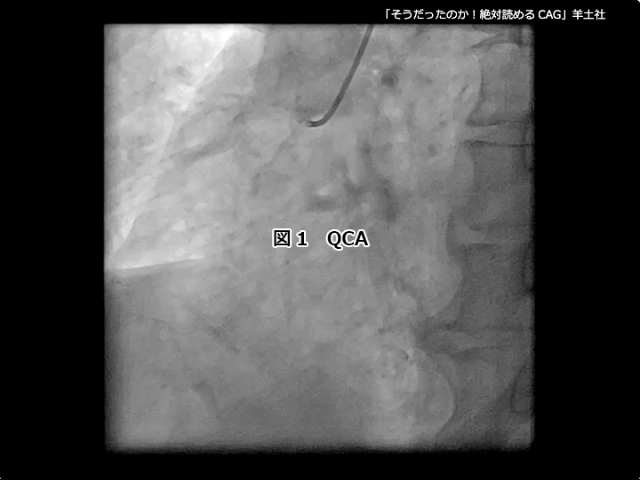

第5章-1 急性冠症候群の造影所見